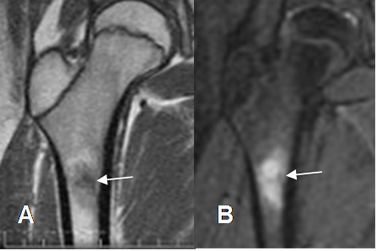

Fig 62. Osteoma osteoide.

A: RM coronal en T1 y B: RM coronal en STIR. Osteoma osteoide hipointenso en T1 e hiperintenso en STIR, con nido central hipointenso.